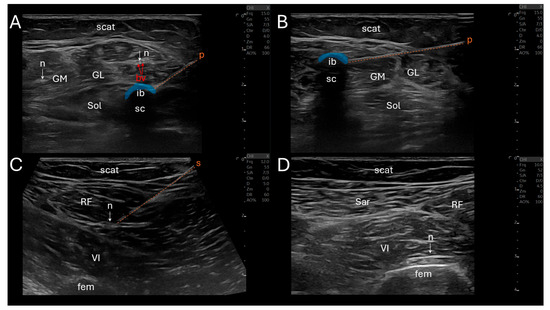

Elucidating its dynamic interaction within the knee joint, this exploration delves into the awareness regarding the articularis genus muscle for ultrasound-guided suprapatellar recess injections. While injections into the infrapatellar recess may proceed without ultrasound guidance, we highlight concerns regarding the potential cartilage injury. [...] Read more.

Elucidating its dynamic interaction within the knee joint, this exploration delves into the awareness regarding the articularis genus muscle for ultrasound-guided suprapatellar recess injections. While injections into the infrapatellar recess may proceed without ultrasound guidance, we highlight concerns regarding the potential cartilage injury. In contrast, especially with ultrasound guidance, suprapatellar recess injections significantly mitigate this risk, especially in the case of collapsed recess. Originating from the distal femur and vastus intermedius, the articularis genus muscle influences the tension of the suprapatellar recess during knee motion. Sonographically identifying this muscle involves visualizing the slender linear structure of the suprapatellar recess, with guidance on differentiation from the vastus intermedius. We provide a succinct approach to ultrasound-guided suprapatellar recess injections, emphasizing needle insertion techniques and strategies to prevent fluid accumulation. In conclusion, this study serves as a concise clinician’s guide, underscoring the significance of the articularis genus muscle’s sonoanatomy in ultrasound-guided suprapatellar recess injections. Ultimately, procedural precision and patient safety can be advanced in this aspect. Full article